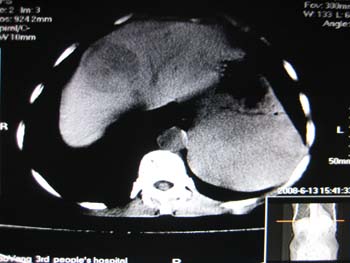

女,65岁,左上腹痛。

肝脏占位  脾脏及胰腺病变   请提供病史

肝脾胃左肾胰都显示不正常啊

病史不详,肝、脾、胰都有占位,谁是原发?

淋巴瘤及肝癌(转移瘤?)可不可以不用一元论解释呢。

胰腺癌伴脾脏侵犯并肝内转移可能性大  建议增强扫描  否则没有确凿的依据

考虑姨尾癌,腹膜后转移\\肝转移

没有病史,没有强化,那就只有猜了,我看病灶很像肝、脾及腹腔多发脓肿,这只是我的意见,

图像欠清,病灶与胃脾胰肾上腺关系显示欠清,建议增强,肝脏考虑转移瘤.

多脏器占位,腹膜后淋巴结增大,淋巴瘤?建议增强扫描